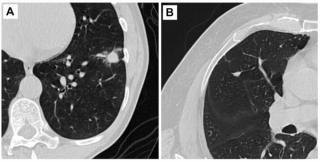

New research shows that incorporating the CT vascular sign into assessments of pulmonary nodules led to significant increases in specificity and accuracy as well as reduced false positive rates for differentiating between malignant and benign solid pulmonary nodules.